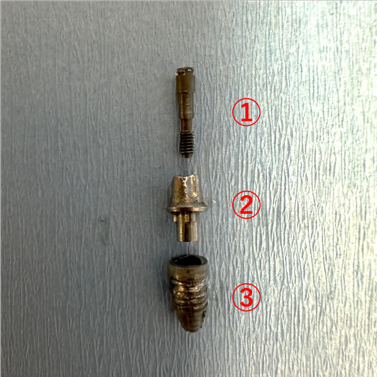

インプラント対と内冠を結合しているスクリュー(図①)を除去しなくてはなりません。他院様で埋入したインプラント体であったので、あらかじめ患者様にどこのインプラントメーカーなのかを聞いておいていただきました。これがわかるのとわからないのではえらい差があります。スクリューをスクリュー除去ドライバーを使用して除去しました。

続けてスクリューが除去できたら、内冠(図②)を外します。これもスクリューが除去できたらそんなに外すのが難しくありませんでした。

最後にインプラント対(図③)を除去します。これにインプラント体除去用キットを使用しました。インプラント体に除去するための道具を食い込ませて、回転させてながら除去しました。除去後はインプラントが埋まっていた部位に対してしっかりと不良肉芽の掻爬および洗浄を行い術式を終了しました。